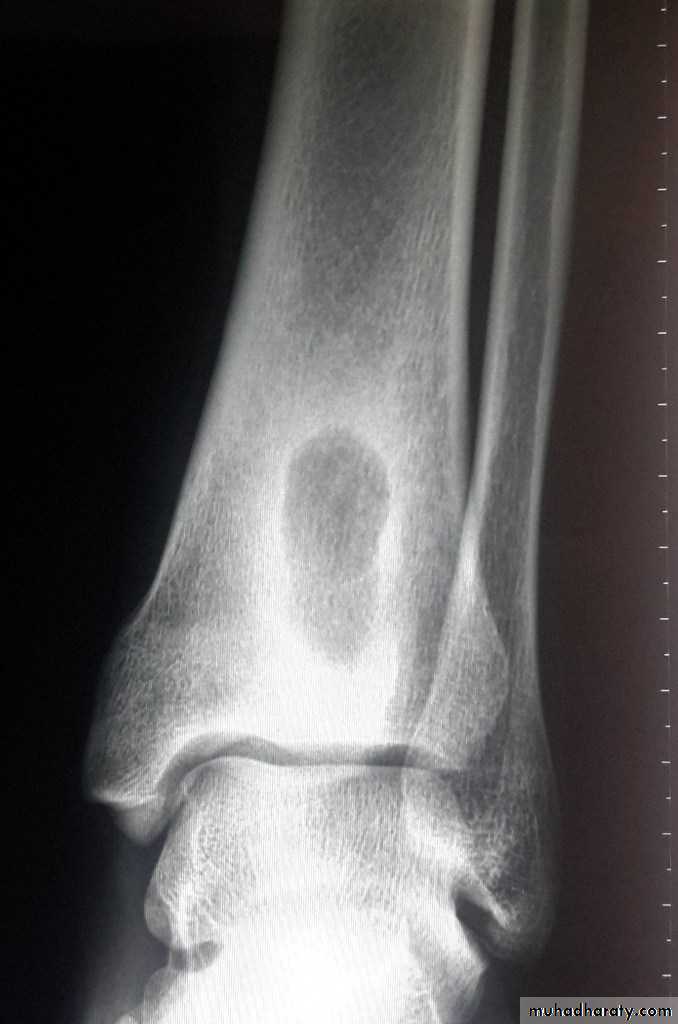

Brodie's abscess

There is a well defined cavity in cancellous bone containing seropurulent fluid, rarely pus. Pain is the predominant symptom.

X-ray: round or oval radiolucent ‘cavity’ 1–2 cm in diameter surrounded by zone of sclerosis, the rest of bone is normal. Treatment is surgery.